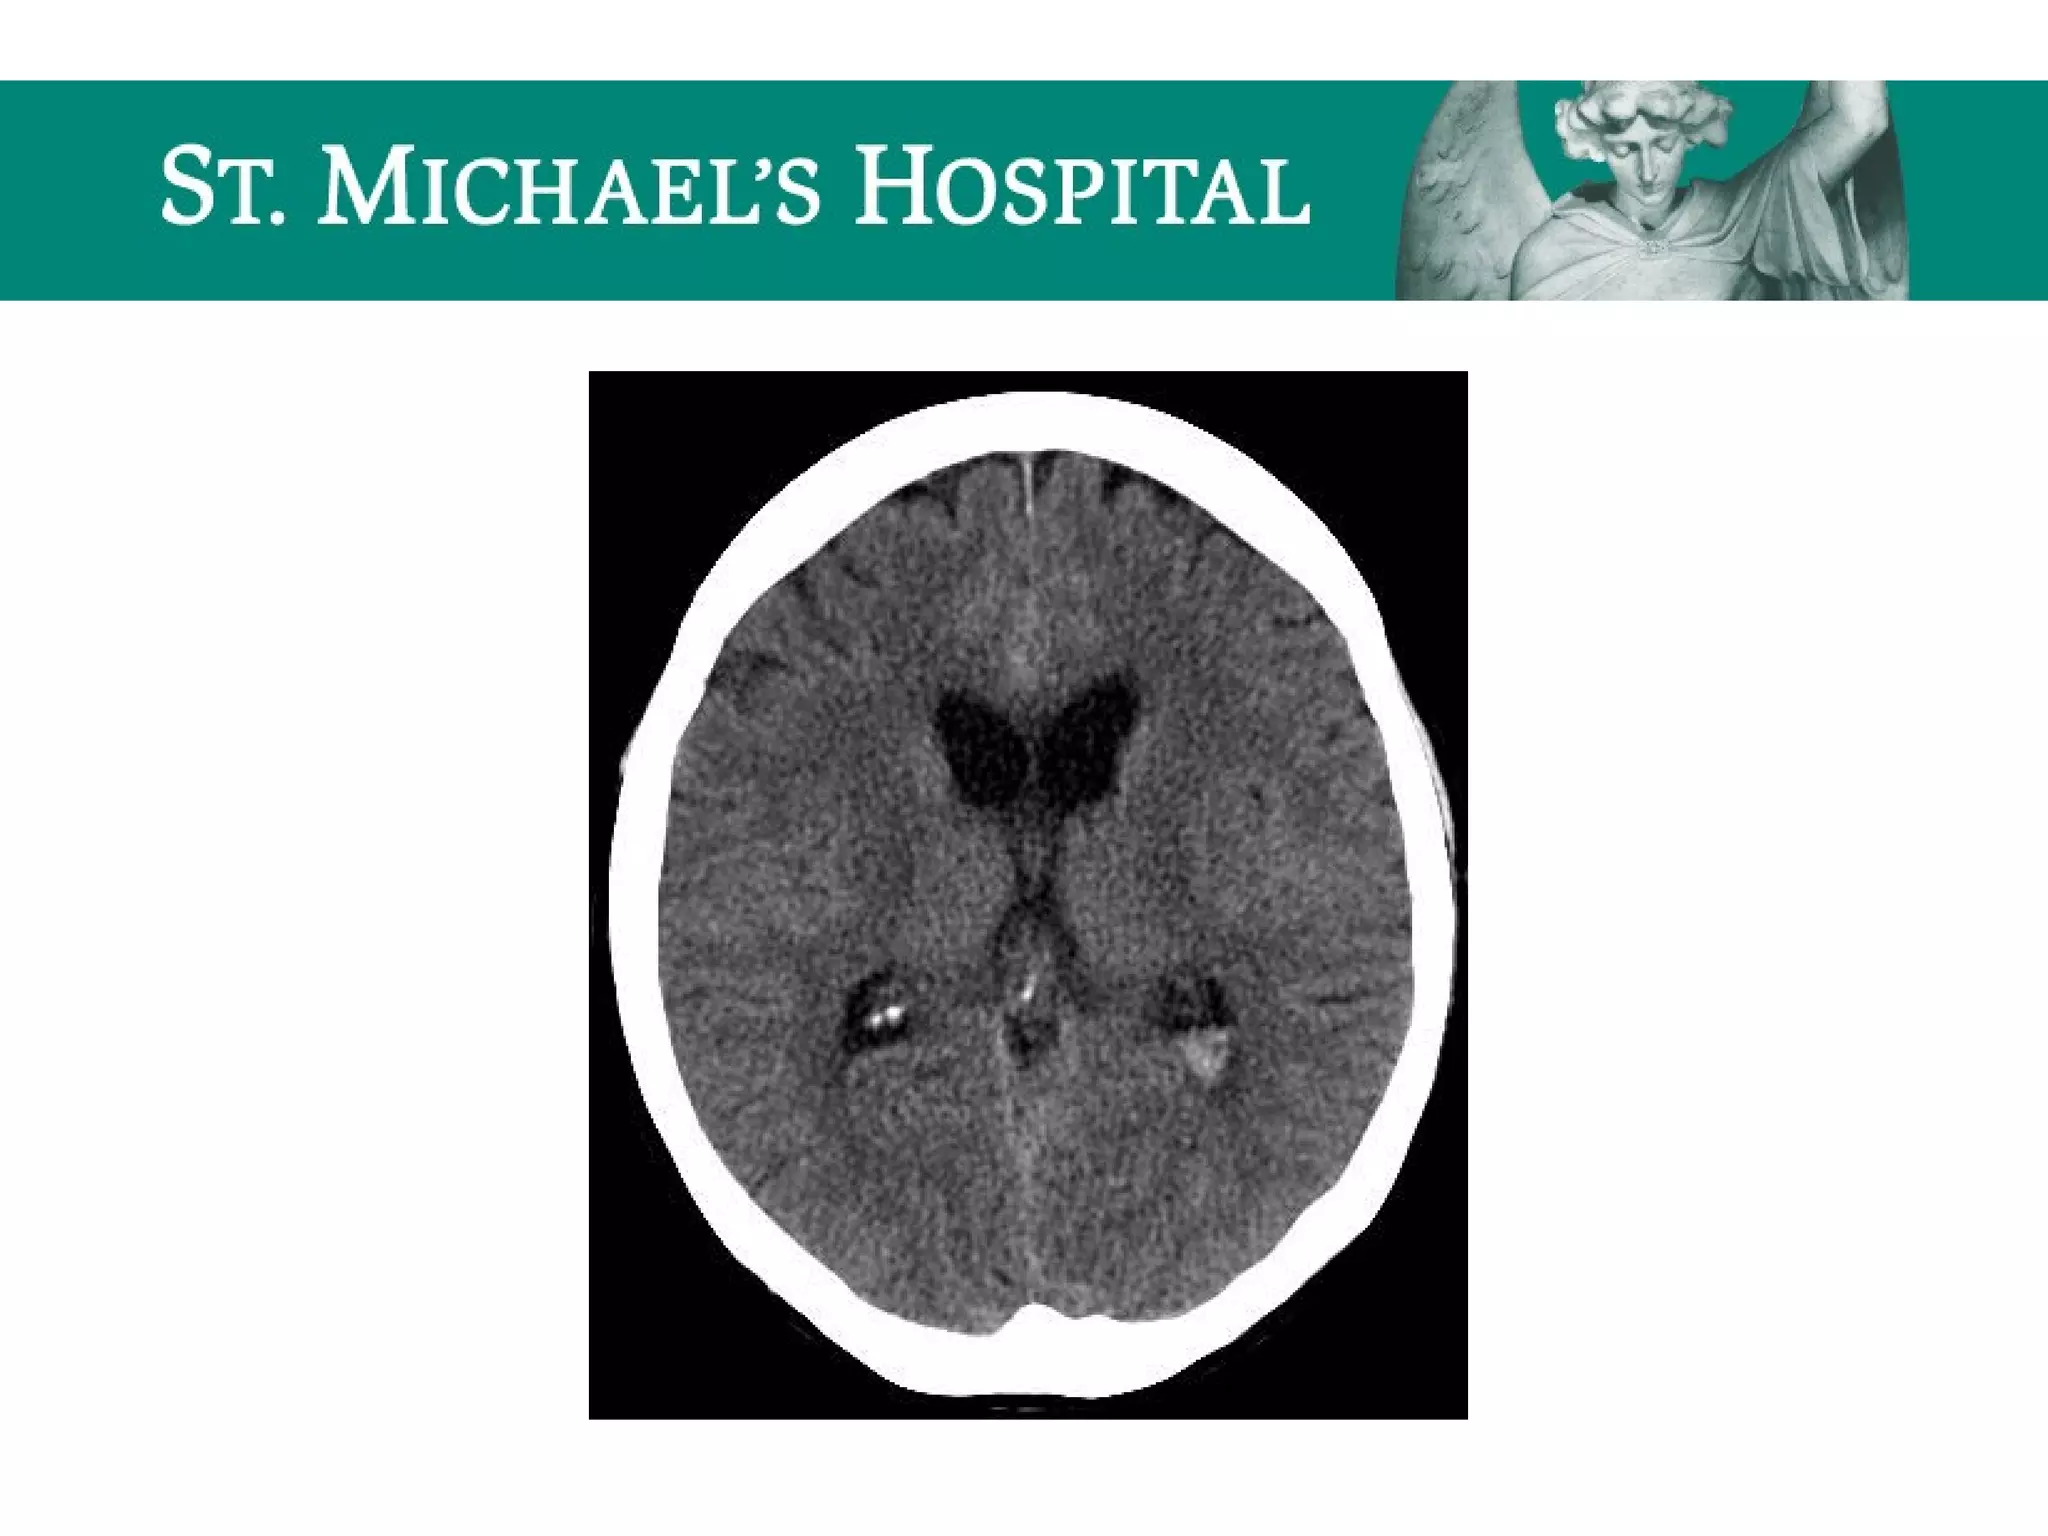

Intra-ventricular Hemorrhage (IVH)

 Layers dependently in the occipital horns

SAH – RadiologicalFeatures  Aneurysms (85% anterior circulation); common locations:  ICA terminus, P.comm. junction, MCA bi/tri-furcation, A.comm, basilar tip  Unenhanced CT:  Highly sensitive for acute SAH (Sn~98% w/in 12 hours, 93% w/in 24 hours)  Location of SAH correlates directly with the location of the aneurysm rupture in ~70% – eg. A.comm. aneurysm rupture  blood in interhemispheric fissure  Most sensitive areas for identification of SAH: – interpeduncular cistern – posterior aspects of Sylvian fissures – occipital horns of lateral ventricles

Intra-ventricular Hemorrhage (IVH) Etiology:  Rupture of sub-ependymal veins  Reflux from SAH  Extension of parenchymal blood  Increased risk of hydrocephalus (interferes with CSF absorption at the arachnoid granulations)  Layers dependently in the occipital horns